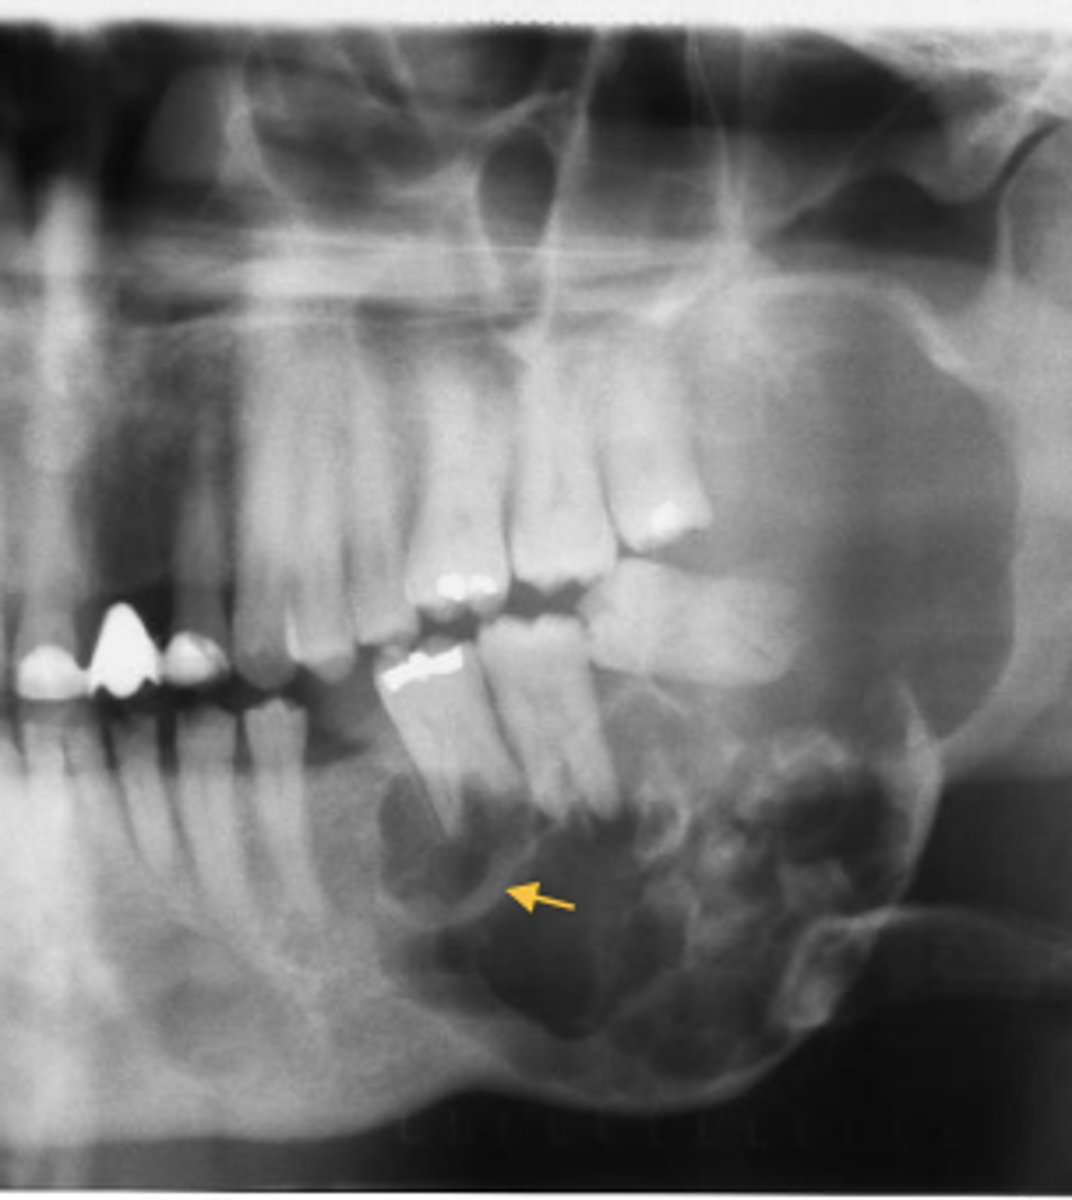

What are radiographic features of ameloblastic fibromas?

⢠unilocular/multilocular radiolucency

⢠usually associated with unerupted tooth (75%)

What are radiographic features of ameloblastic fibro-odontomas?

⢠well-defined radiolucency + radiopaque component

*small fleck to large calcified masses